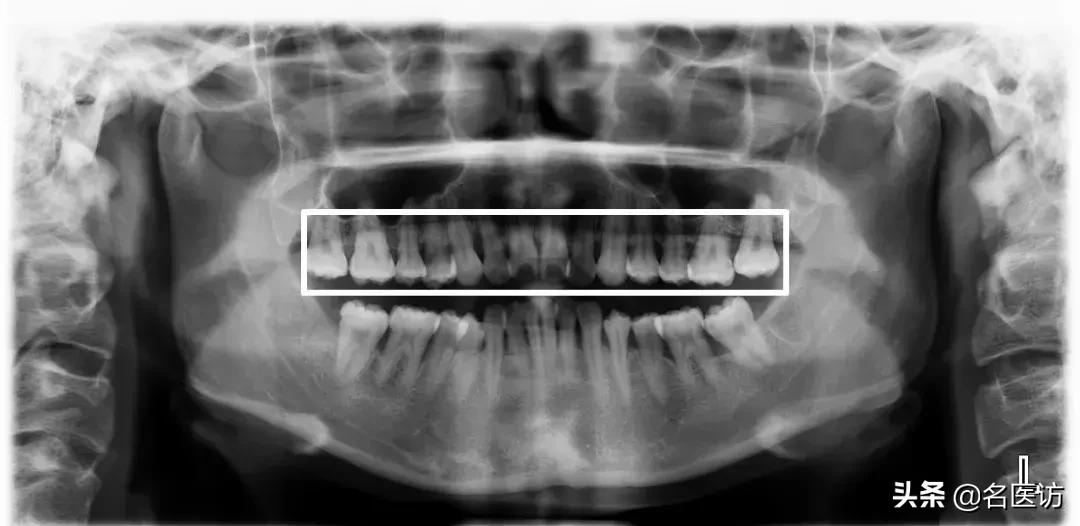

1、牙根、牙槽骨

牙根和牙槽骨的状态是影响矫正方案的2个重要因素。

牙根短

我们平常肉眼可见的“牙齿”,其实只是整颗牙齿的“冰山一角”,看不见的牙根部分也很重要。如果存在严重牙根吸收或牙根短的情况,矫正中移动牙齿的风险就会增加,牙齿可能会松动。

牙槽骨吸收

若牙根健康,但牙槽骨存在吸收情况,矫正时也是一样有风险的。如果把整个牙根分成3份,健康的牙根是全部埋在牙槽骨中的,当牙槽骨吸收超过1/3时,矫正就可能带来牙齿松动,而当牙槽骨吸收超过1/2,一般就不建议做矫正了。